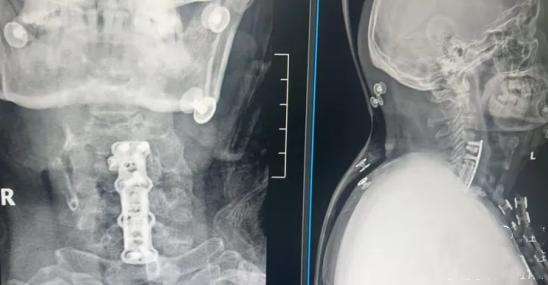

最后运用个性化定制3D打印钛网+融合器,重建脊柱稳定性,精准修复颈椎生理曲度。这样不仅有利于加速植骨融合,还能有效保障手术远期疗效。

经过积极治疗和康复后,罗先生恢复速度远超预期。曾经走路不稳、随时可能瘫痪的他,慢慢能够下床、站立、独立行走,身体一天天向好!术后复查影像资料显示:脊髓恢复了正常形态,椎管减压非常成功!后续进一步进行康复治疗,重返工作岗位、重回事业巅峰,指日可待!